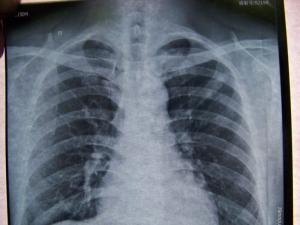

疾病检查

陈旧性肺结核陈旧性肺结核胸片。

诊断鉴别

陈旧性肺结核陈旧性肺结核根据胸片可确诊。